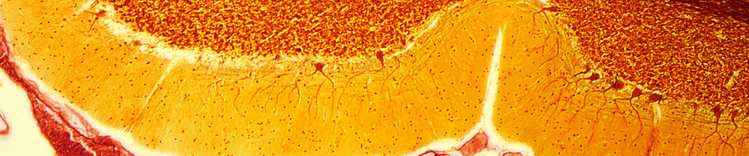

PURKINJE CELLS IN CEREBELLUM

Changes in the aging brain

Physical changes in the brain associated with aging include:

- Atrophy (shrinkage) of tissue in some regions

- Increased ventricular volume

- Loss of neurons and synapses and reduced formation of new neurons

- Accumulation of abnormal proteins